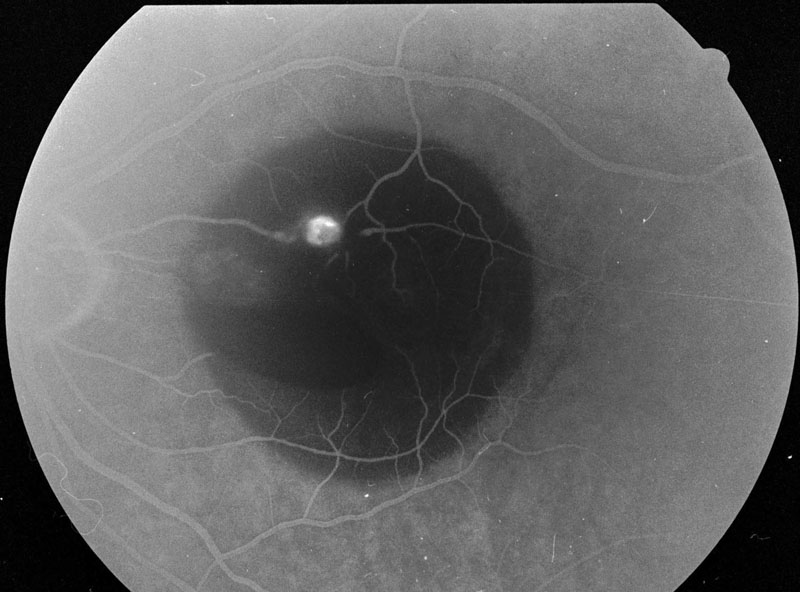

36. ábra Artériális macroaneurisma következtében a maculatájon prae- és subretinális vérzéseket alakultak ki. A funduskamerával készített felvételen a nyíl a macroaneurismára mutat, a nyílhegy a hátsó üvegtesti kéreg praemacularis foramenjét jelzi. A foramen körül az üvegtesti kéreg gyűrűszerűen megvastagodott. A biomikroszkópos vizsgálat a gyűrű temporális felének elemelkedésével járó részleges hátsó üvegtesti leválást talált. Feltételezhető, hogy a macroaneurisma rupturáját a kóros vitreoretinális adhaesio provokálta.

37. ábra A késői fluorescein angiográfiás fényképen a macroaneurisma területében körülírt festékkilépés figyelhető meg.